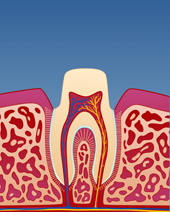

Om man over lengre tid har vært plaget med tanngnissing, vil man kunne se dette på tennene. Disse blir slitt og får rette kanter. Man kan også slite seg gjennom det ytterste laget på tannen (emaljen), slik at tannbenet (dentinet) blir synlig. Dette kan føre til at tennene blir mer ømfintlige og følsomme i det daglige.

Tanngnissing/ -pressing kan også medføre slitasje på fyllinger, samt bidra til utvikling av sprekkdannelser i tennene.

Ved langvarig og alvorlig tanngnissing, kan tennene etter hvert bli svært slitt. Dette kan gå ut over både tennenes funksjon og utseende. I slike tilfeller kan det være nødvendig å bygge opp igjen tennene enten ved hjelp av plastfyllinger eller med kroner i porselen (fig. V-VIII). Dette kan være kostbar og omfattende behandling og kan i enkelte tilfeller utløse støtte fra Helfo. Det er tannlegen som vurderer om tilstanden er så alvorlig at den omfattes av dette regelverket.